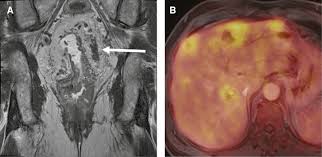

Imaging Of Colorectal Cancer The Clue To Individualized Treatment from www.degruyter.com Staging tests may include imaging procedures such as abdominal, pelvic and chest ct scans. Ct scan result colon cancer staging. Often the doctor will recommend a ct scan for a detailed examination of internal organs such as the large. A ct scan can often detect evidence of a growth or tumor. Colon cancer refers to cancer diseases that occur in the large and small intestine. If my own mother asked me what she should do to prevent colon cancer, i would tell her to this test is essentially a cat scan of the colon, designed to find large polyps and cancers. Find out about symptoms and risk factors for colon cancer, also called colorectal cancer. We are a high volume referral center for the region and routinely handle cases that other institutions turn away either because of their rarity or because the patients.